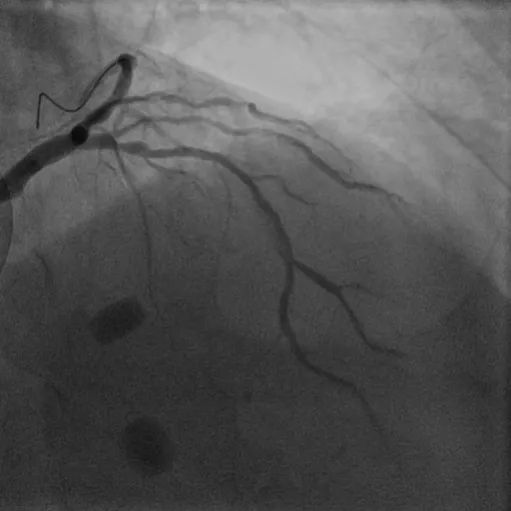

LAD长弥漫钙化病变:患者70岁男性,因间断胸痛3天入院,既往高血压病史、长期吸烟史,诊断不稳定型心绞痛。冠脉造影显示前降支近中段弥漫性狭窄伴钙化,应用冠脉腔内影像学技术-IVUS对该血管进一步评估,结果显示:前降支多处180-270°钙化,中段钙化结节(红色箭头所示)。顺利送入3.0*12mm Shockwave冲击波球囊至LAD中段,充盈4atm使球囊充分贴壁,显示球囊近段膨胀不良,随着冲击波能量释放,球囊逐渐扩张,膨胀扩张满意。先后对LAD多处钙化病变进行8个周期(80次脉冲)预处理,应用IVUS评估显示钙化处出现钙化断裂。该患者多处弥漫钙化病变,在IVUS指导下联合Shockwave冲击波球囊实现精准预处理,为后续支架植入奠定了基础。果然,送入长支架通过病变顺畅,释放扩张未感觉明显阻力即到位,支架膨胀舒展,成功植入支架。IVUS结果显示支架膨胀贴壁良好。

术前冠脉造影

植入支架后